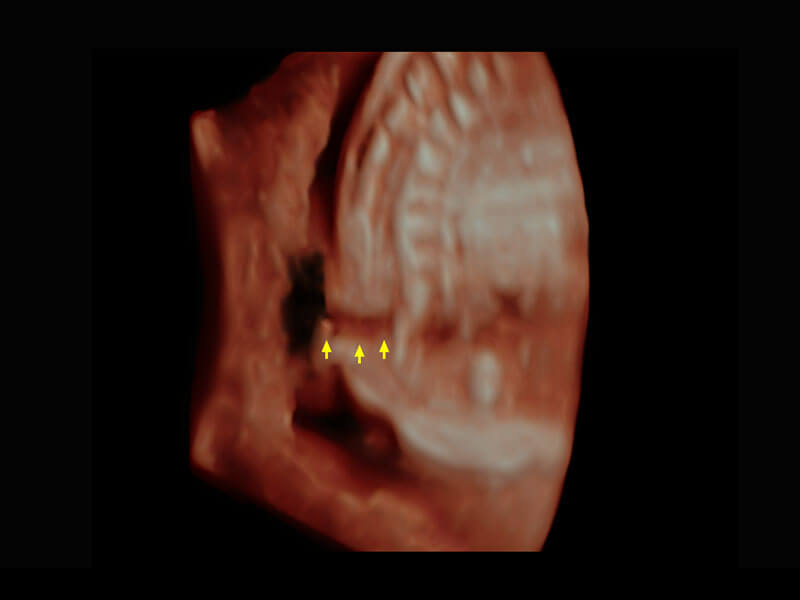

腔内三维-宫内节育器

右室双出口

胎心容积成像